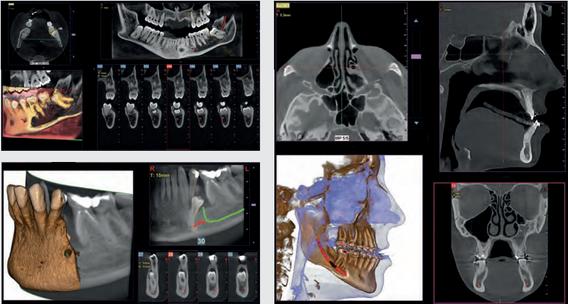

Maximum flexibility for your diagnoses Hyperion X9 pro is fully configurable and its modular and scalable design makes it possible to transition from a basic to a more advanced version in an easy and costeffective manner. An extraordinary platform that adapts to the needs of your dental practice thanks to the 2D PAN/CEPH sensor, which can be easily relocated, and the reversible teleradiographic arm which can be installed on both sides Moreover, the standard 2D sensor can be replaced with the innovative direct conversion DCIII sensor to provide SuperHD images with low doses The most versatile extra-oral 3-in-1 imaging device on the market. Perfect for ultra-high quality 2D and 3D exams with very low doses

FOVs with a 10 cm diameter are essential for the study of impacted third molars because, in an adult of medium build, the distance between the third molars on the left and right, including the respective roots, the alveolar process and the surrounding bone, is at least 9 cm Reduced fields of view are useful when analysing impacted or supernumerary teeth in order to restrain the dose to the region of interest For a correct treatment planning it is indeed crucial to determine the actual position (vestibular or palatal) This is only possible with a 3D analysis, even at a very low dose, with the QuickSCAN protocol The complete 13 x 16 cm field of view allows for an accurate assessment of the upper airways, which is often useful to complete the investigation for an orthodontic treatment that does not neglect ENT problems.

Position the equipment directly on the 3D model, combine it with the STL data from intraoral scanners and define the final prosthetic project With the advanced implant planning tools* you will be able to operate safely thanks to accurate information on the amount of bone and the distance from the surrounding anatomical structures, such as the mandibular canal, defining a minimum safety distance

1 Orthogonal panoramic X-ray: minimises the overlapping of adjacent teeth and provides better periodontal analysis

2 Fast panoramic X-ray: low dose and reduced scan time, perfect for primary investigations, follow-ups or uncooperative patients

3 Child panoramic X-ray: limited exposure and optimised parameters for fast paediatric examinations.

4. Complete dentition divided into quadrants: localised investigations with selectable segmentation to limit the irradiated dose.

5. Bitewing projections limited to crowns: high resolution and low dose, a comfortable alternative to intraoral imaging, appreciated by patients with a strong gag reflex.

Temporomandibular joints: right and left, with open or closed mouth, and in latero-lateral and posteroanterior projections with multi-angle projection

Innovative DCIII technology, which improves depth of field and increases contrast - and therefore real resolution power - lets users obtain SuperHD panoramic images from extremely extensive datasets to provide an 11-layer MultiPAN. Highly useful in the case of complex morphologies

Maxillary sinuses

Frontal or left/ side view, with optimised trajectory